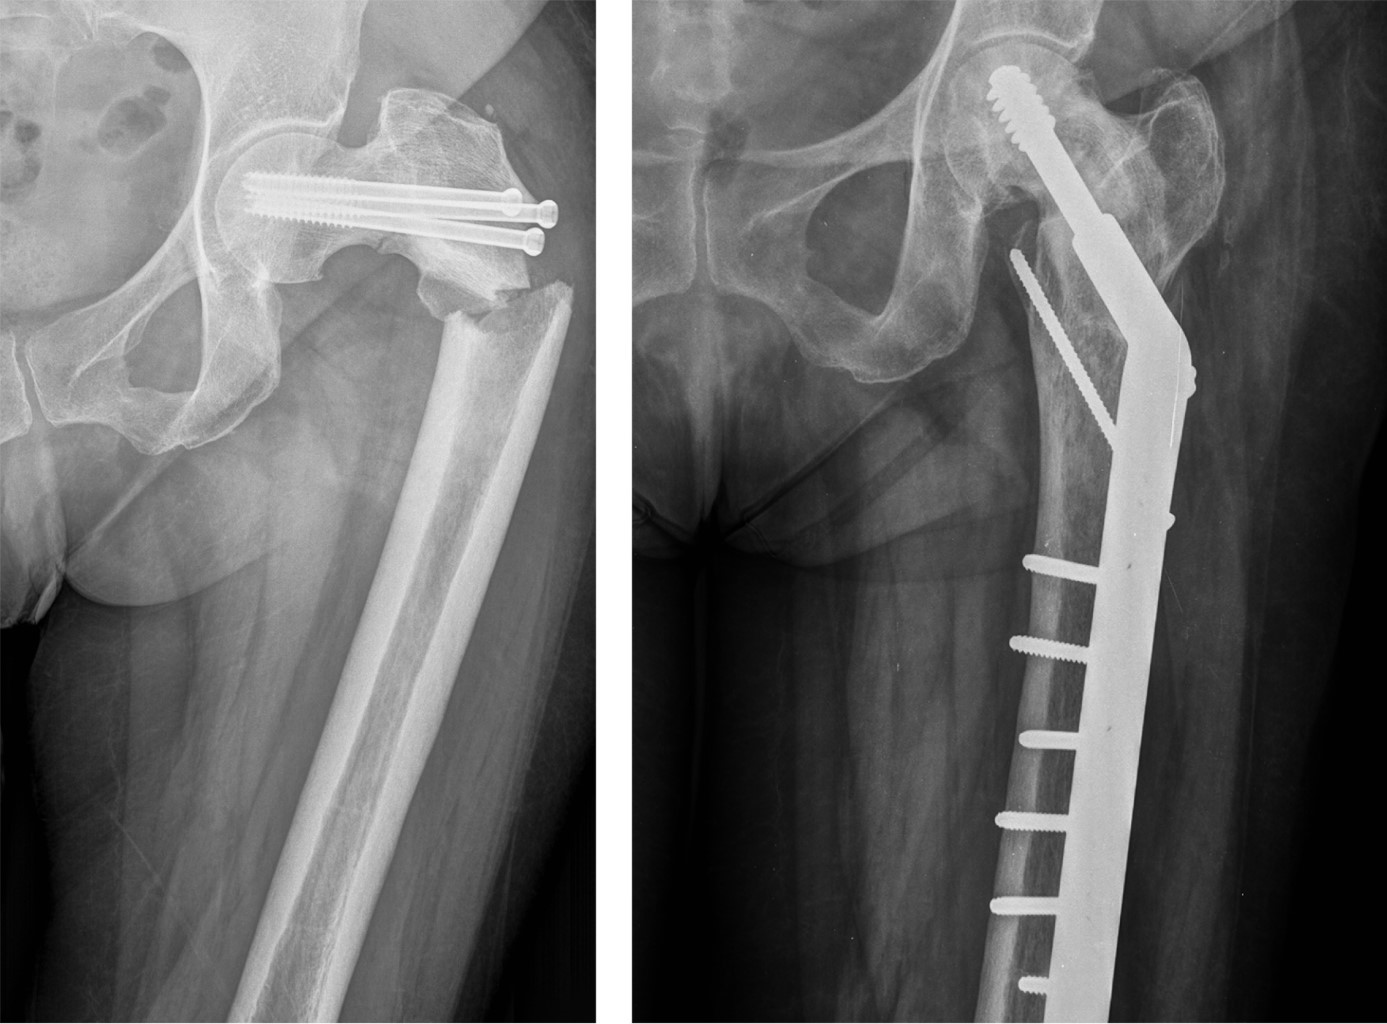

Periosteosynthesis subtrochanteric fractures after fixation of femoral neck fractures with cannulated screws

Introduction: the objective of this study was to analyze the incidence and predisposing factors in subtrochanteric fractures on hips previously treated with cannulated screws after suffering a subcapital fracture, based on eight cases registered in the last 20 years. Material and methods: this is a retrospective observational study on a series of patients with a diagnosis of subtrochanteric hip fracture, who have been treated in recent months for a subcapital fracture of the same hip by osteosynthesis with cannulated screws. The study period was 20 years (2000-2020). Results: of the eight cases, five were women and three were men, with a mean age of 75.12 years (range 59-87 years). In all cases, the subtrochanteric fracture occurred within a year after the first fracture, the time elapsed between the two fractures was four months on average (range 1-9 months). Regarding the disposition of the cannulated screws, most of the 7/8 cases were in the shape of an upper vertex triangle, and only one case was in the shape of an inverted triangle or lower vertex. The entry point into the femoral external cortex was at the level of the lesser trochanter in six cases, and in two cases this entry was distal to the lesser trochanter. Conclusion: in our experience, in the etiology of subtrochanteric fractures, the introduction of screws distal to the lesser trochanter, and the distribution of the screws in a triangular shape are the two main objective predisposing factors.

Figure 3

Figure 4